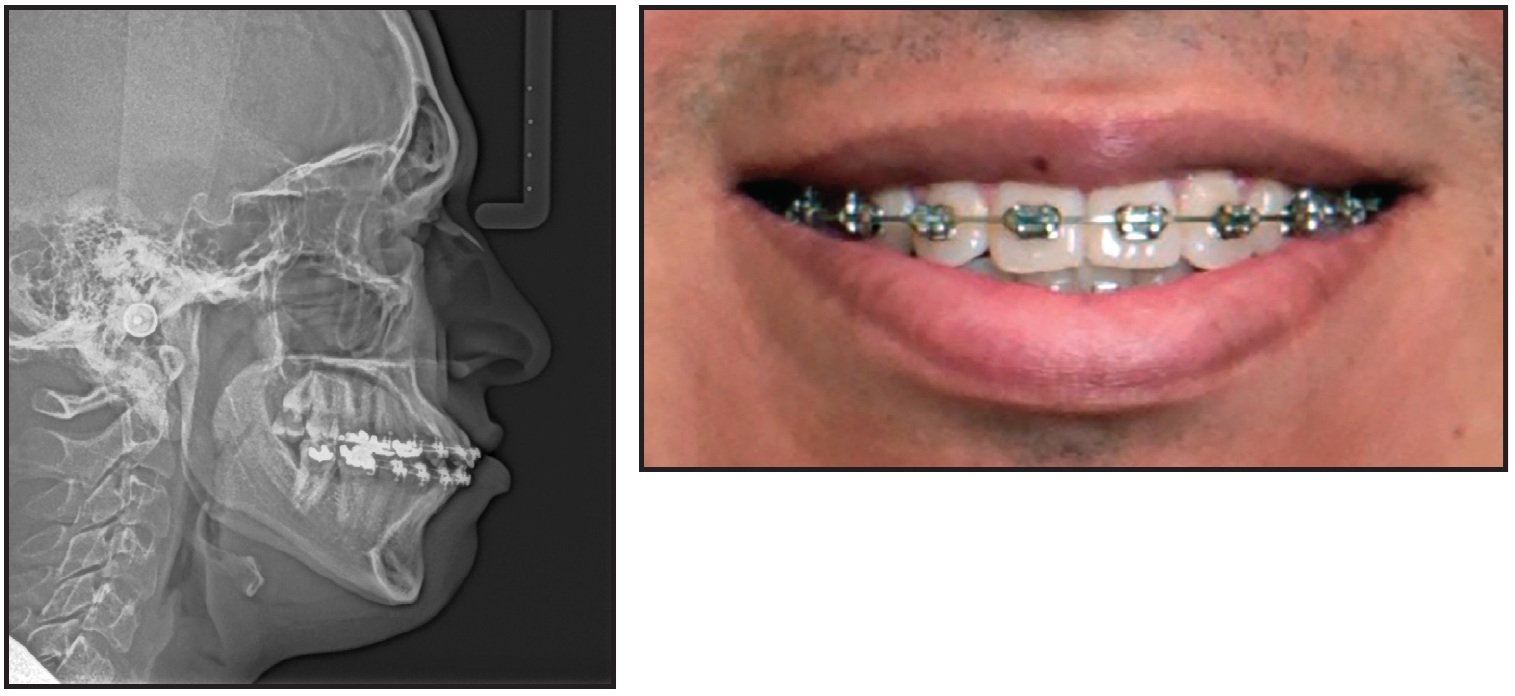

Case 2, in progress at seven months, demonstrates the effect of SAP bracket positioning on the wire plane and the resulting smile arc (Figs. 11-13).

Fig. 11 Case 2. 52-year-old male patient with reverse smile arc and “hanging” canines before treatment.

Fig. 12 Case 2. Initial bonding with SAP bracket positioning.

Fig. 13 Case 2. After seven months of treatment. Lower arch will continue to level.